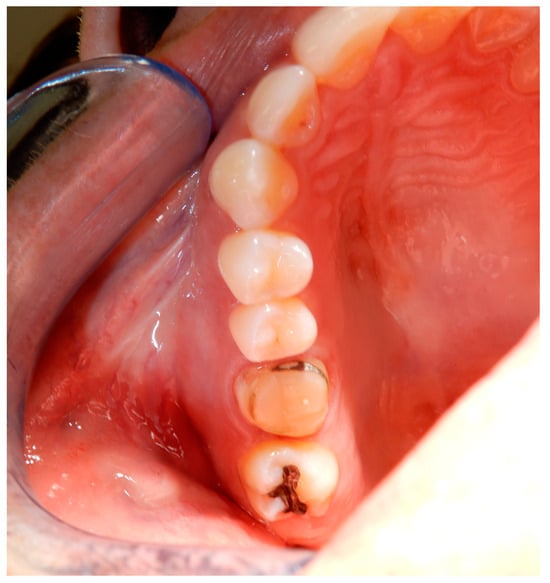

3.2. Case Report